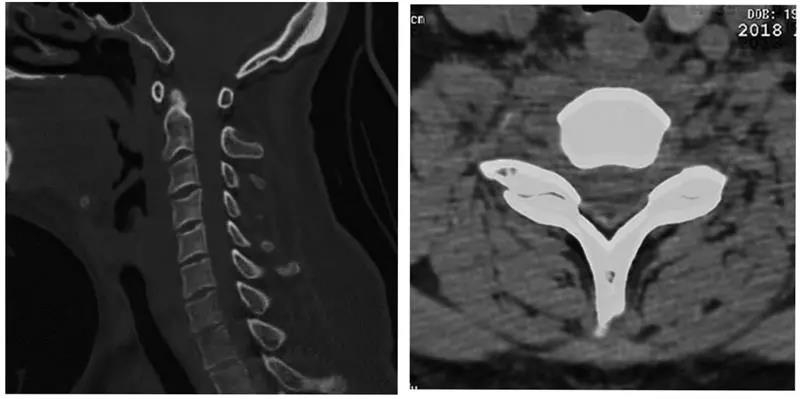

术前CT

术前核磁